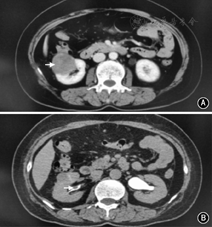

共有24例患者纳入本研究,患者中位年龄是69.5岁(48~79岁)。19例男(79.2%),5例为女(20.8%)。10例(41.7%)有吸烟史。主要症状是肉眼血尿14例(58.3%);10例患者是无症状的,通过体检发现肿瘤。经过B超,CT和膀胱镜等检查,21例患者术前诊断为肾癌并发尿路上皮癌,2例术前仅诊断为肾癌,1例术前仅诊断为输尿管癌。肾癌+上尿路尿路上皮癌7例(29.2%),肾癌+膀胱癌15例(62.5%),肾癌+上尿路尿路上皮癌+膀胱癌2例(8.3%),肿瘤平均直径3.3(0.6~8)cm,有2例远处转移。1例典型的肾癌并发同侧肾盂癌患者的CT见图1;图2显示了1例肾癌并发膀胱癌患者的CT表现。